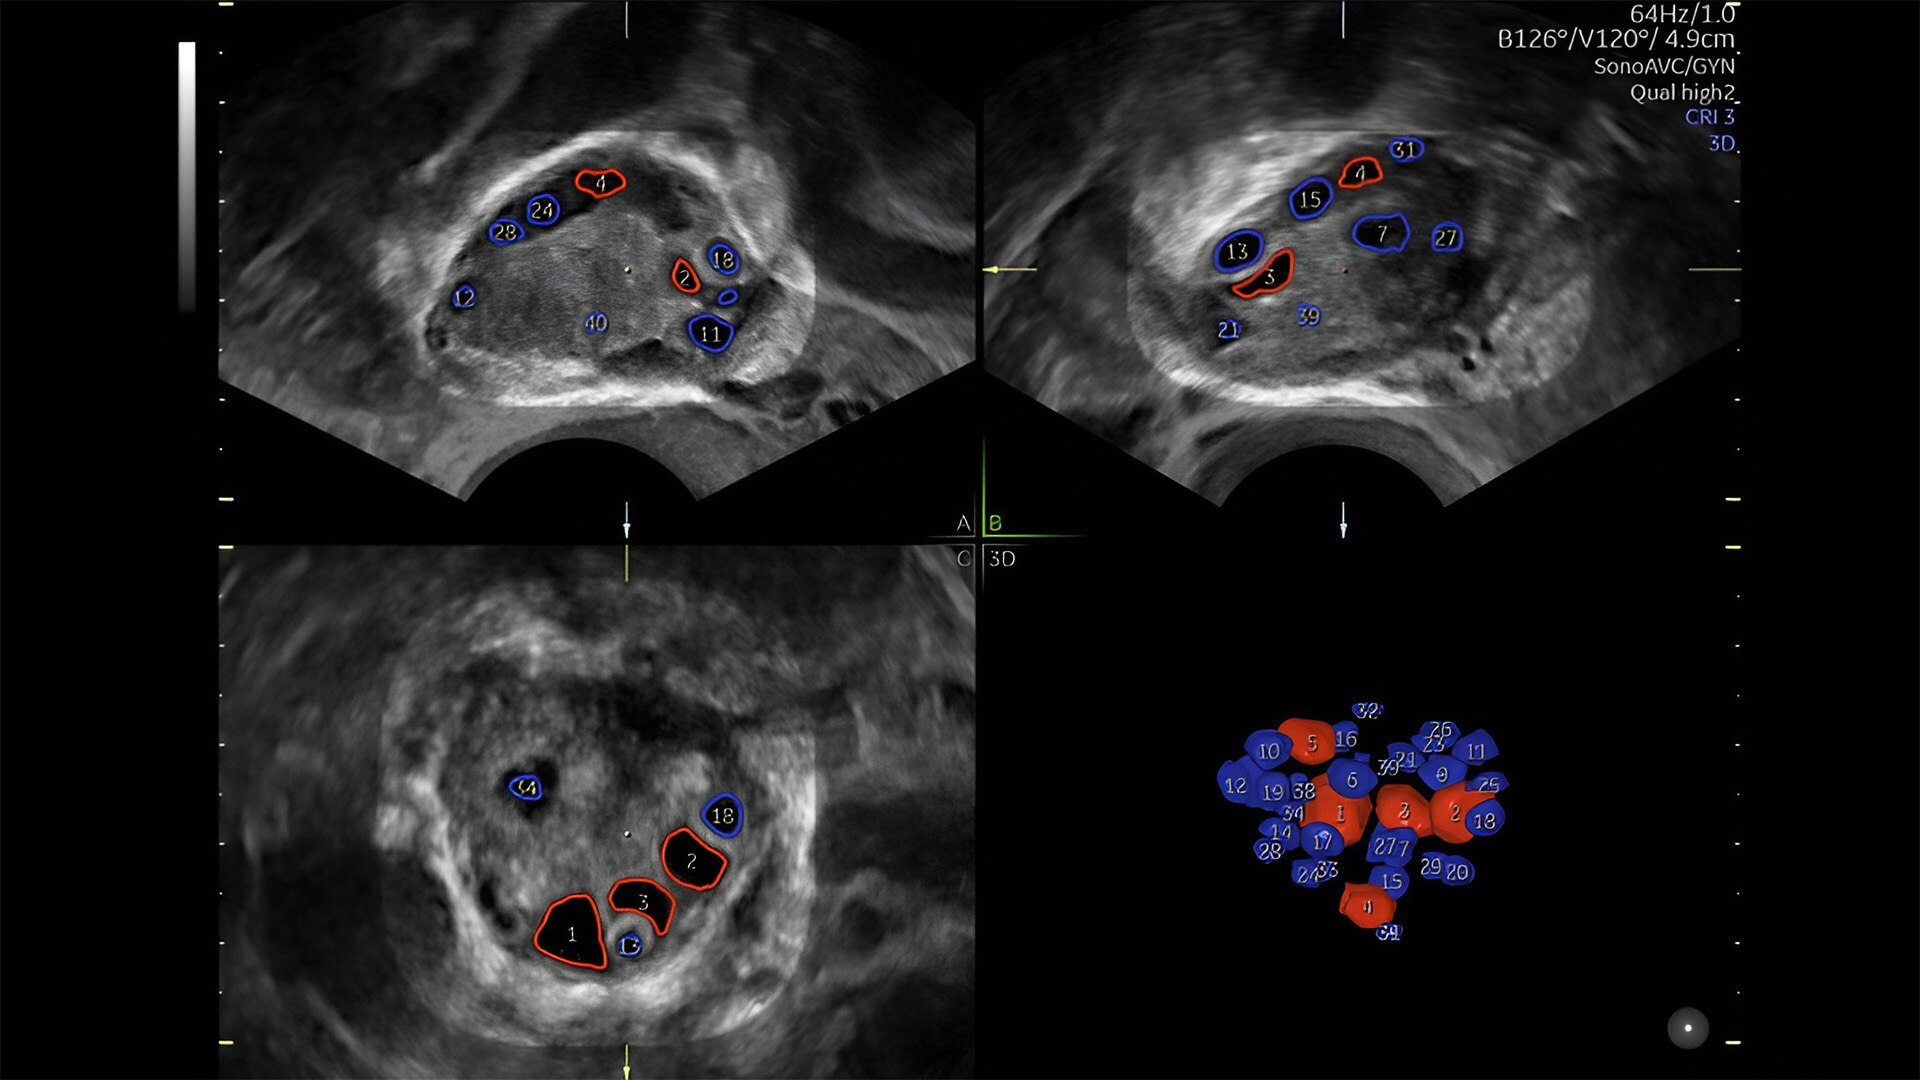

Pelvic health

Offer patient answers faster with Ai-based automation tools

Complex cases come with enough uncertainty. That's why the Voluson Expert 22 is specifically designed for in-depth assessment of complicated anatomy — with pioneering first trimester, fetal cardiac, gynecological, and other pivotal technologies that focus on early detection and intervention.